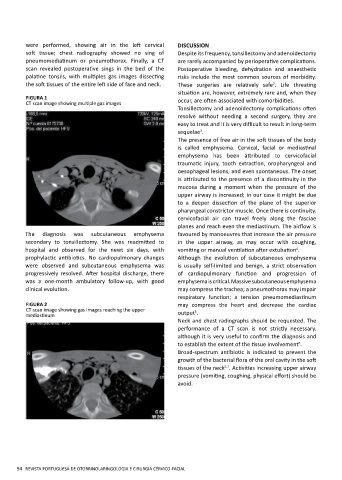

FIGURA 1 occur, are often associated with comorbidities.

CT scan image showing multiple gas images

were performed, showing air in the left cervical DISCUSSION

scan revealed postoperative sings in the bed of the Postoperative bleeding, dehydration and anaesthetic

palatine tonsils, with multiples gas images dissecting risks include the most common sources of morbidity.

the soft tissues of the entire left side of face and neck. These surgeries are relatively safe . Life threating